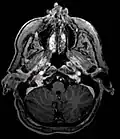

Ectopic functional paraganglioma (glomus jugulare) in a patient with VHL. T2 weighted MRI at the same location demonstrates a high signal mass consistent with a paraganglioma. Extra adrenal paragangliomas can be found in VHL (arrow). -